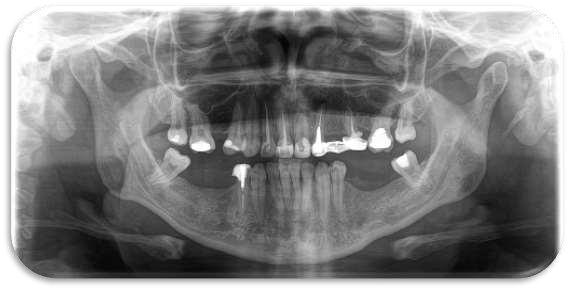

El quiste de retención mucoso del seno maxilar es una lesión benigna, generalmente asintomática, que se detecta de manera incidental en estudios radiográficos. Se presenta el caso de un paciente en el que, durante una radiografía panorámica de rutina, se identificó una imagen radiopaca bien delimitada en seno maxilar izquierdo compatible con quiste de retención mucoso Se discuten las características radiográficas, el diagnóstico diferencial y las consideraciones clínicas en el manejo de este hallazgo

Reporte de caso

Paciente masculino, de 35 años, acude para valoración odontológica general Se realizó radiografía panorámica como parte del examen inicial En el seno maxilar izquierdo se observó una imagen radiopaca de límites definidos, redondeada, localizada en la pared inferior del seno No se observaron signos de destrucción ósea ni desplazamiento de estructuras adyacentes

El paciente no refirió síntomas respiratorios ni dolor en la región. Con base en las características radiográficas, el hallazgo fue diagnosticado como quiste de retención mucoso en seno maxilar izquierdo. Se indicó control clínico y tomografía, al no requerir tratamiento quirúrgico inmediato.

Introducción

El QRM es una entidad benigna, autolimitada y habitualmente asintomática. Radiográficamente se presenta como una opacidad homogénea, redondeada, en el interior del seno maxilar, sin comprometer la arquitectura ósea.

El diagnóstico diferencial incluye sinusitis crónica, pólipos antrales y lesiones quísticas odontogénicas que invaden el seno Sin embargo, la ausencia de sintomatología y la apariencia radiográfica típica orientan hacia un QRM

La mayoría de los casos no requiere tratamiento, siendo suficiente el seguimiento clínico-radiográfico

En el corte tomográfico oblicuo–sagital derecho se observa: (figura 3)

Imagen hipodensa, bien delimitada, de contorno redondeado, ubicada en el seno maxilar derecho.

La lesión parece originarse desde el piso del seno, con íntima relación con los ápices dentarios superiores posteriores.

No se aprecian signos de erosión ósea marcada, aunque existe adelgazamiento del piso sinusal

La densidad es homogénea, lo que orienta hacia un contenido quístico

Seno maxilar derecho: ocupándolo parcialmente, se identifica una imagen hipodensa, bien delimitada, de contorno redondeado y homogéneo, compatible con lesión quística

Produce expansión con adelgazamiento de la pared ósea sin clara evidencia de destrucción.

El quiste de retención mucoso del seno maxilar es un hallazgo frecuente en radiografías panorámicas de rutina Su reconocimiento es importante para evitar diagnósticos erróneos y procedimientos innecesarios El seguimiento radiográfico constituye la conducta adecuada en pacientes asintomáticos